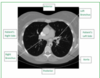

Label this normal CT.

Label these CT scans of the patient.